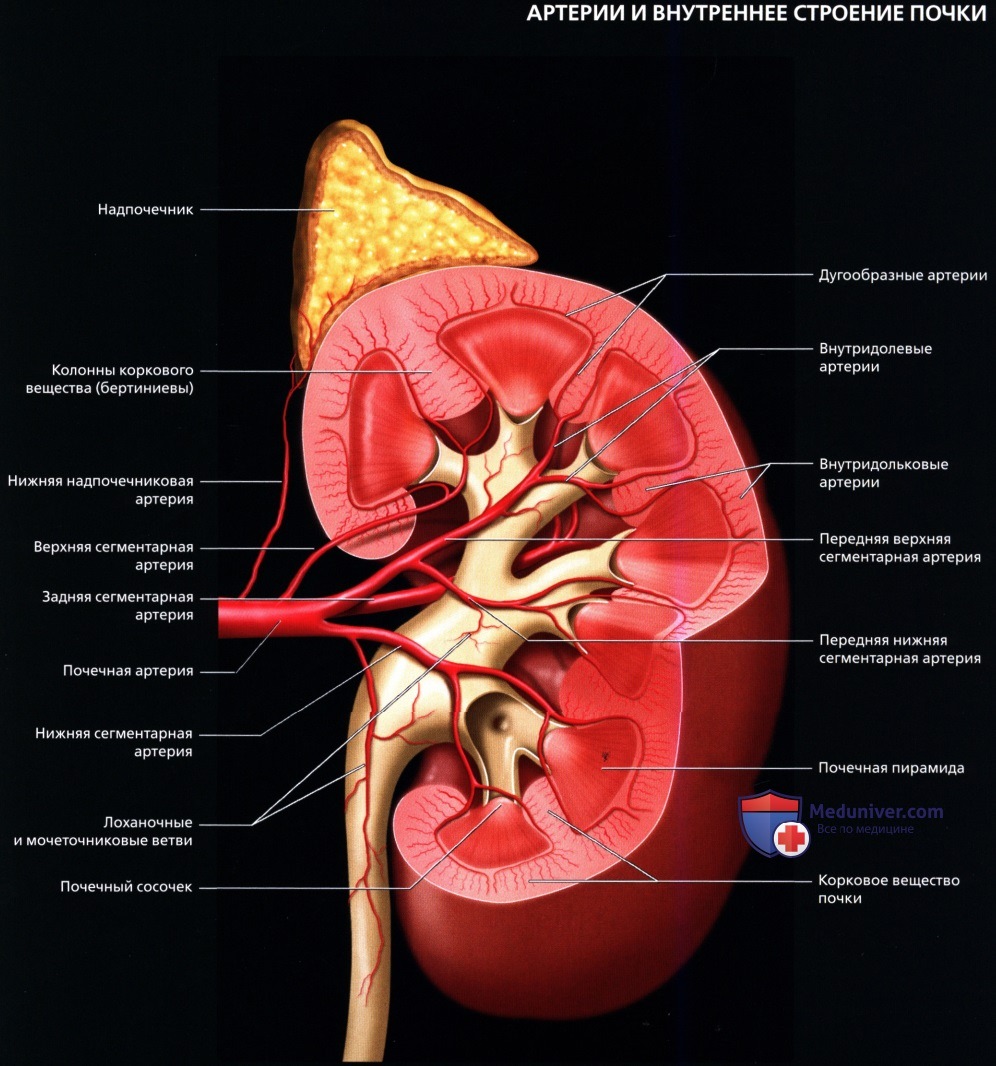

а) Анатомия почек:

2. Топографическая анатомия почки:

3. Внутренняя структура:

• Почки можно рассматривать как полый орган, просвет которого занят жировой тканью, почечной лоханкой, чашечками, сосудами и нервами

• Ворота почки: сюда подходят артерия и вена и выходит мочеточник

• Почечная лоханка: расширение верхнего конца мочеточника в виде воронки:

о Собирает мочу от больших чашечек (2 или 3), каждая из которых в свою очередь собирает мочу от малых чашечек (2-4)

• Почечный сосочек: точечная верхушка почечной пирамиды, содержащей собирательные трубочки, выделяющие мочу

о Каждый сосочек открывается в малую чашечку

• Корковое вещество почки: периферическая часть, содержит почечные (клубочки, сосуды), проксимальные части собирательных трубочек и петли Генле

• Мозговое вещество почки: внутренняя часть, содержит почечные пирамиды, дистальные части собирательных трубочек и петли Генле

• Кровеносные и лимфатические сосуды, нервы:

о Артерия:

— Обычно по одной к каждой почке

— Отходит от аорты на уровне L1-L2 позвонков

о Вена:

— Обычно по одной от каждой почки

— Лежит кпереди от почечной артерии и почечной лоханки